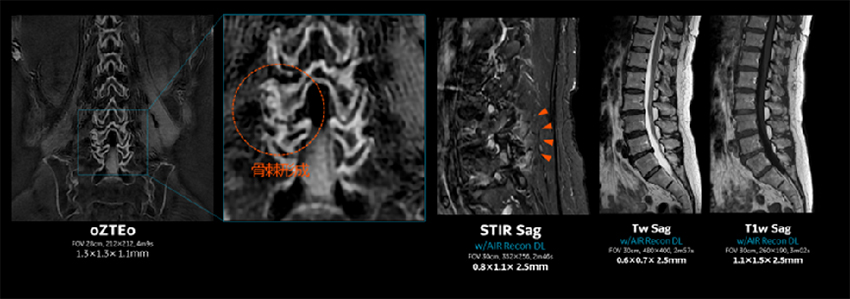

脊椎MRでは矢状断のスライス厚を2.5mmに変更している。脊椎のプロトコルにおいてもThin slice化することで、椎間孔の微細構造が描出され、脊柱管から外側に流れる神経根を連続的に追うことが出来る。

Pironeer_Kosugi_06.jpgFigure. 4

oZTEoにより、一回のMRで炎症性変化と、骨棘形成を同時に観察することが出来る。

MRIで軟部組織の診断と併せて骨情報を得ることが出来ることで、患者さんの一連の検査のワークフローが改善される。Fig. 4は、腰椎のルーチン検査に、oZTEoを追加撮像した症例である。STIRで浮腫が見られる領域に、oZTEoで骨棘が形成されており、浮腫と伴う急性期の変化と、骨棘形成を伴う慢性的な変化の部位に浮腫を伴う急性期の変化が同時に起こっていることが確認されている。これは良く起こりえる病態ではあるが、腰痛の検査の際にMRIとCTをside by sideで読影をすることはほぼなく、oZTEoにより今まで気に留めていなかった病態の変化に新ためて確認することができる。